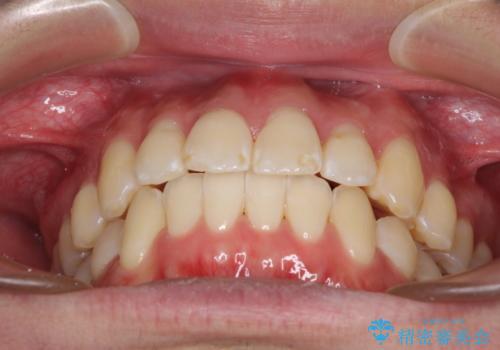

- 前歯のデコボコと若干口元が突出していることを気にして来院された患者様です。

全体的に軽微な叢生が認められ、口元もやや前方に突出していたため、インビザラインでのIPR(歯と歯の間を削る)と歯列全体の後方移動によって歯並びを整えることとしました。

上下ともに歯列の幅が狭かったため、側方に拡大することで前歯のデコボコや突出感を解消するためのスペースを獲得することができました。

歯並びが改善したことはもちろん、咬み合わせの改善まで実感することができ、患者様には大変満足していただけました。